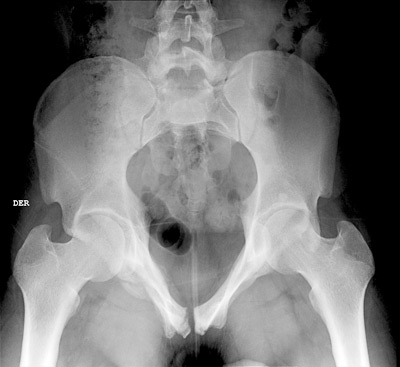

Hoy voy a hablaros de las proyecciones inlet y outlet de pelvis:

- Proyección inlet de pelvis o proyección de entrada de la pelvis:

Esta proyección la utilizamos para visualizar el estado de la articulación sacroilíaca, desplazamientos anteroposteriores y en sacroilíacas y pubis, arrancamientos en espinas ciáticas, tuberosidad isquiática y sacro, fractura de sacro y asimetría en anillo pelviano.

El rayo en esta proyección será paralelo al sacro. El paciente estará situado sobre la mesa de rayos en decúbito supino y en posición anatómica, el rayo central irá dirigido con 60º angulación caudocraneal centrado a 3’8cm sobre el borde superior del pubis. Se obtendrá una imagen de dovela invertida del sacro.

- Proyección outlet de pelvis o proyección de salida de la pelvis:

Esta proyección permite ver la migración superior o inferior de la hemipelvis, fracturas o diástasis del arco anterior, fracturas de sacro (desplazamientos, asimetrías de los agujeros sacros y alteración de las líneas arcuatas), ascenso o fracturas de las articulaciones coxofemorales y desplazamiento cefálico del complejo posterior.

En esta proyección el sacro será perpendicular al plano del sacro. El paciente estará situado en decúbito supino sobre la mesa de rayos en posición anatómica. El rayo central irá dirigido a 45º craneal a 5 cm sobre el borde superior del pubis.